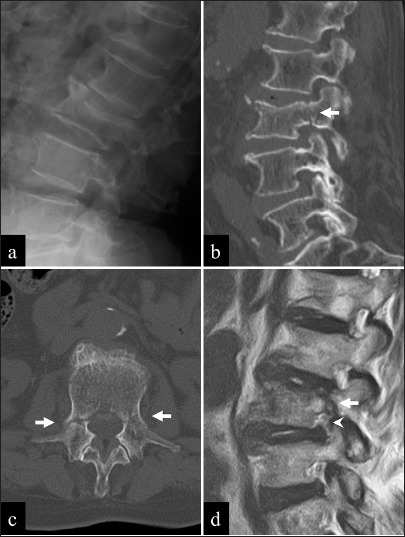

Case description: An 81-year-old osteoporotic female presented with low-back pain without any history of trauma or prior spinal surgery. Computed tomography revealed an OVF at L3, accompanied by bilateral pedicle fractures. Conservative treatment failed, and she successfully underwent early balloon kyphoplasty at L3, plus stand-alone percutaneous pedicle screw fixation. Postoperatively, symptoms were relieved, and she was discharged without complications on postoperative day 10.